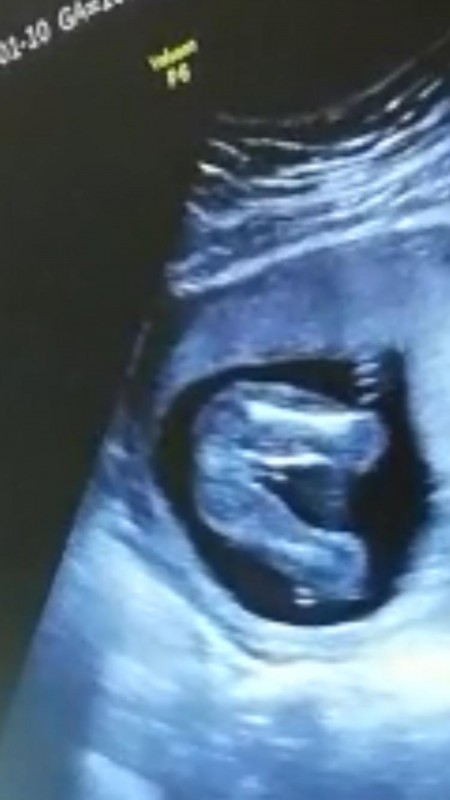

116+5 deyim. Doktor %90 erkek dedi. Cinsiyet değişir mi

Allah bilir tabi de. Bence degismez bariz belli erkek olduğu. Tabi o kordon degil pipi ise :)

Erkek çocuğu daha çabuk bilinir bursada gozukuyor bencede erkek canım saglikli kucagina al

Pipisi ortada belirgin niye degissinki